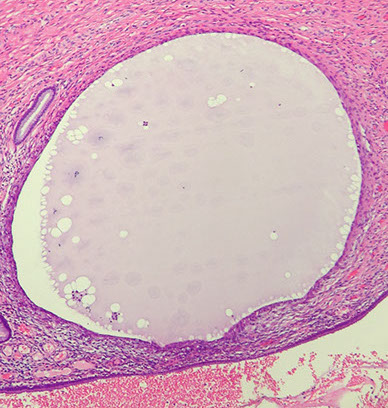

Nabothian cyst

Normal finding caused by obstruction of crypt opening by squamous epithelium thus dilating endocervical glands

- usually superificial but can go deep

- can cause acute/chronic cervicitis

Micro: uniform architecture, no stratification, mits, or atypia

- can cause reactive changes if rupture

Nabothian cysts